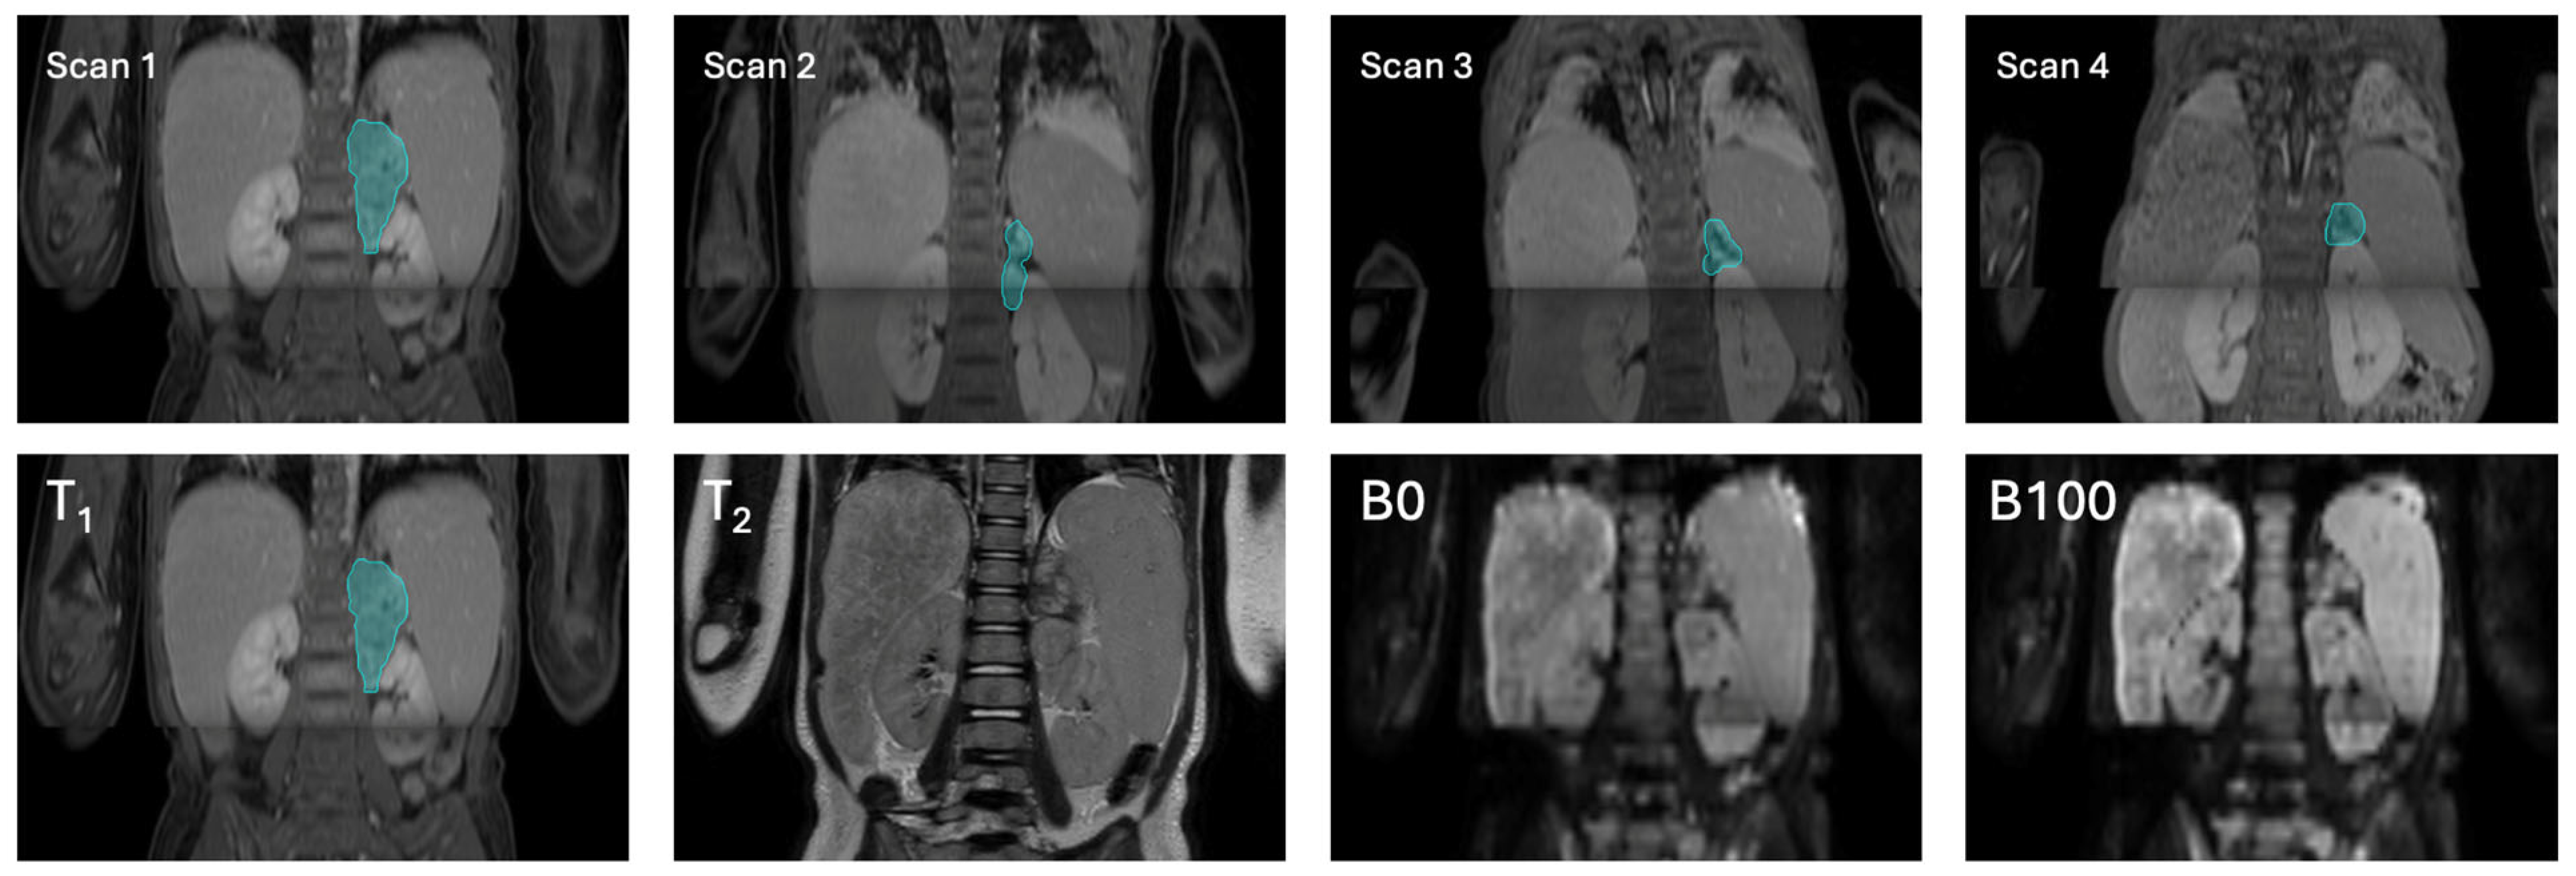

2.2.1. Magnetic Resonance Imaging

| Sequence | T1-Weighted Gradient Echo | T2-Weighted Spin Echo | Diffusion-Weighted Imaging |

|---|---|---|---|

| Repetition time (ms) | 6.1 | 458 | 2537 |

| Echo time (ms) | 2.9 | 90 | 76.4 |

| Voxel size (mm3) | 0.71 × 0.71 × 3 | 0.833 × 0.833 × 1.15 | 1.39 × 1.39 × 5 |

| Dimensions (voxels) | 560 × 560 × Z | 480 × 480 × Z | 288 × 288 × Z |

| b-values (s/mm2) | N/A | N/A | 0, 100 |

| Contrast | Gadovist, 0.1 mmol/kg body weight | - | - |